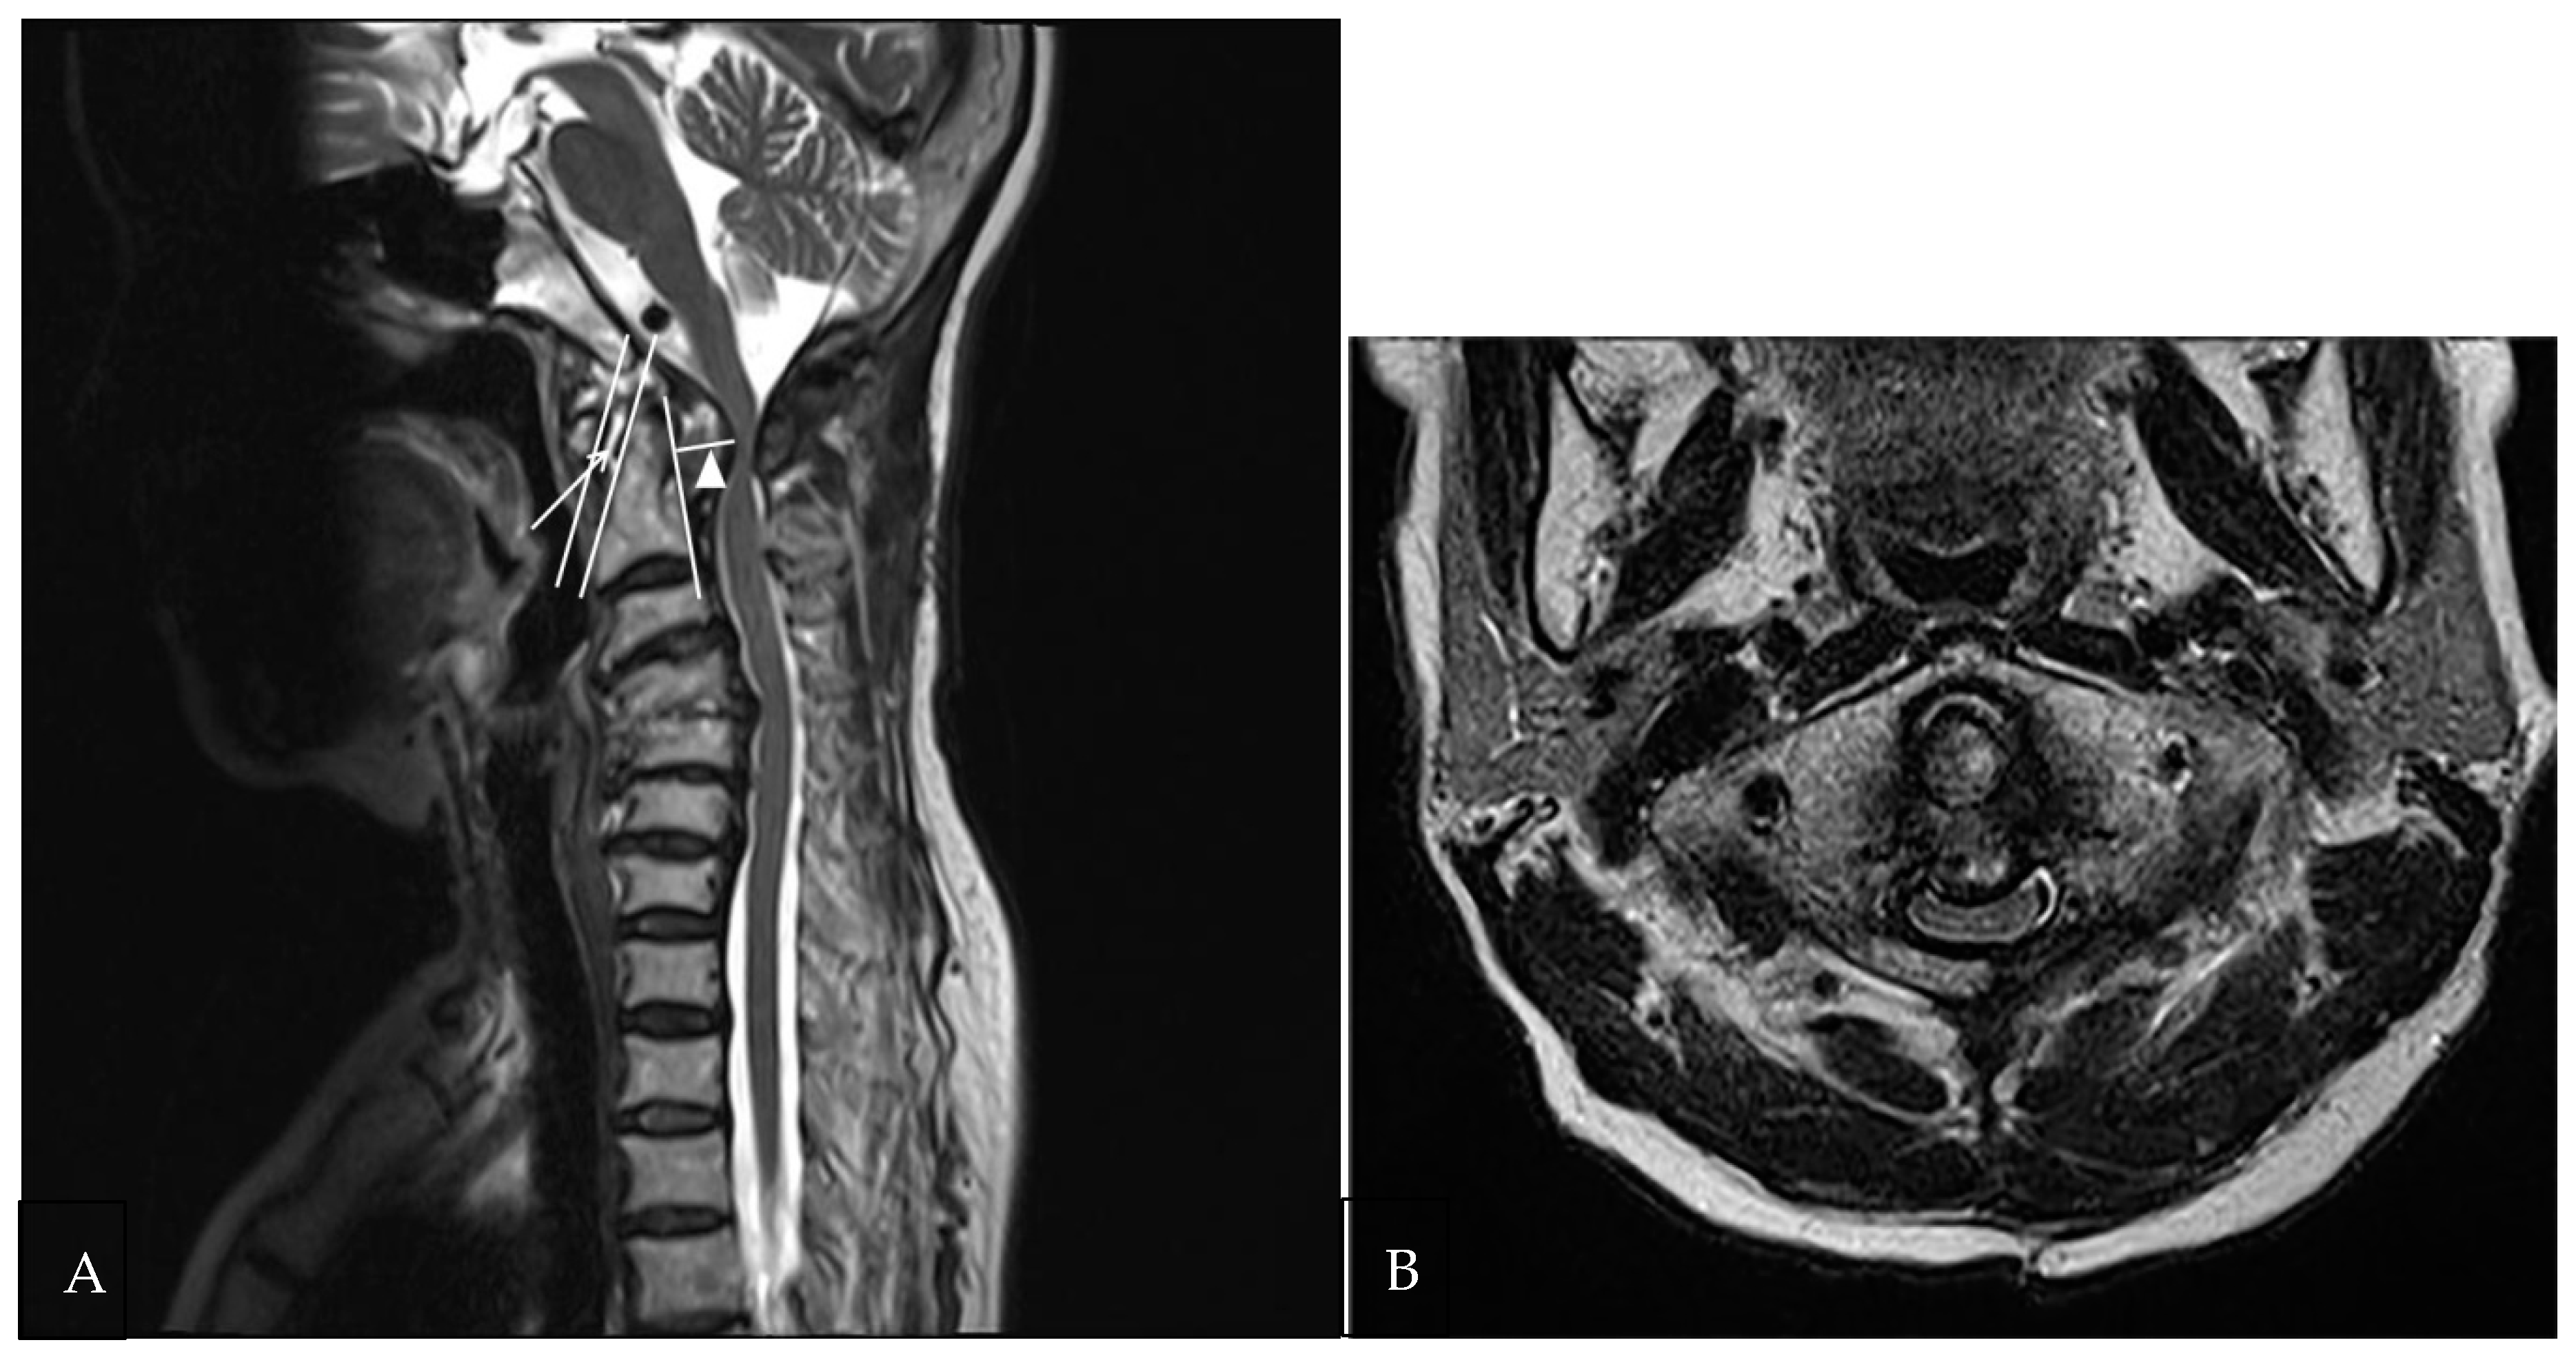

| Axial diameter (mm) | 10.05 ± 3.47 (3.2–17.4) | 4. 68 ± 1.64 (2.0–8.3) | <0.0001 |

| Longitudinal diameter (mm) | 23.53 ± 6.04 (14.1–46.7) | 16.99 ± 3.42 (12.19–24.1) | <0.0001 |

| Pre-odontoid space (mm) | 2.78 ± 1.49 (1.16–7.6) | 5.54 ± 2.17 (3.1–11.1) | <0.0001 |

| Retro-odontoid space (mm) | 9.25 ± 3.25 (4.1–16.0) | 5.19 ± 1.76 (2.8–10) | <0.0001 |